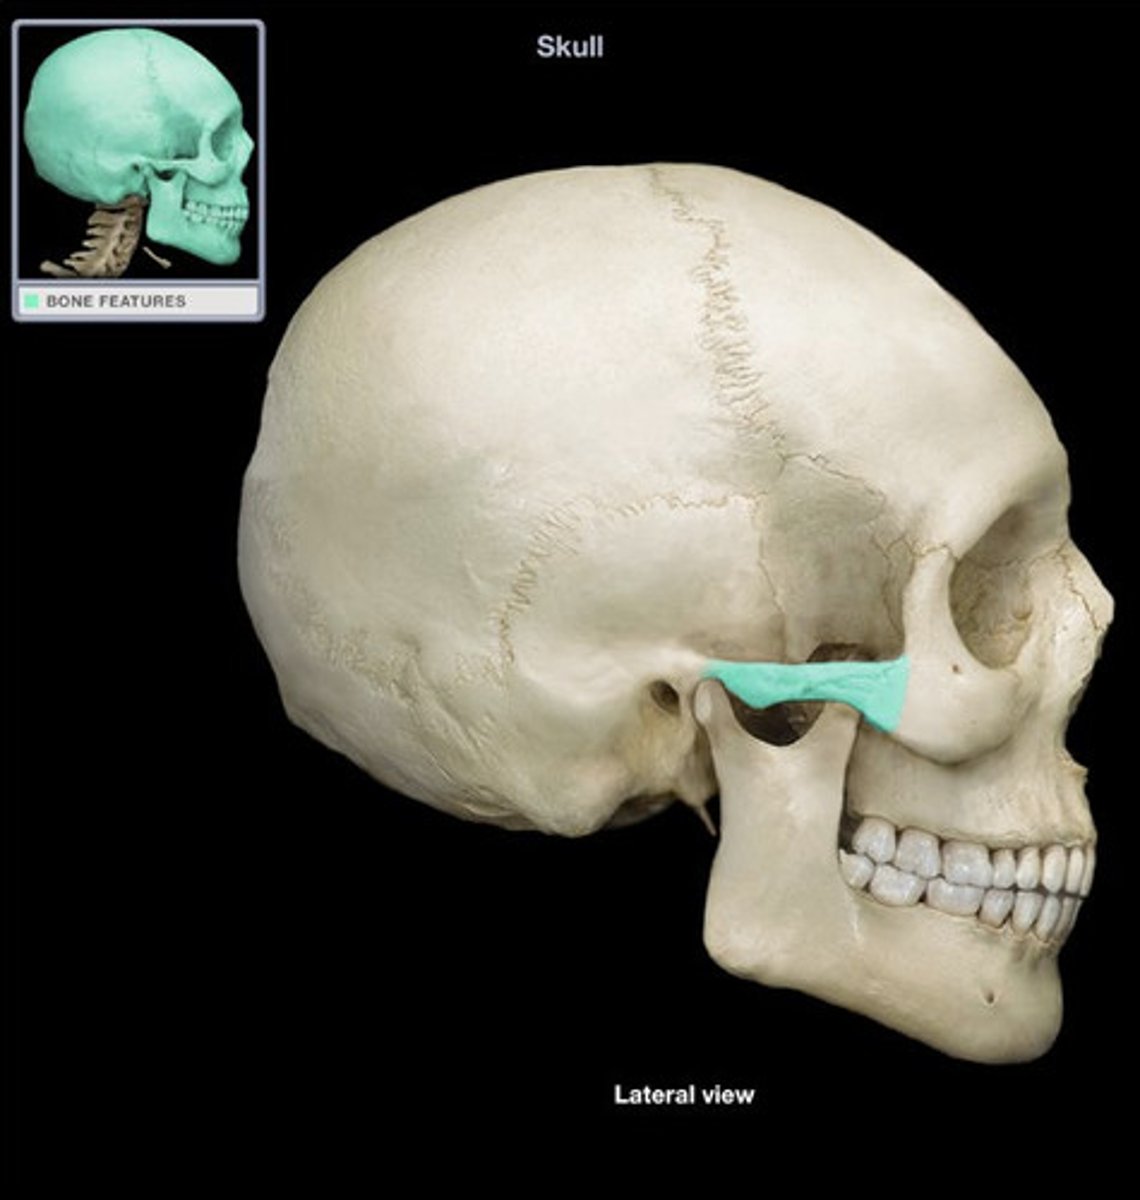

zygomatic process

temporal process of zygomatic bone

zygomatic arch